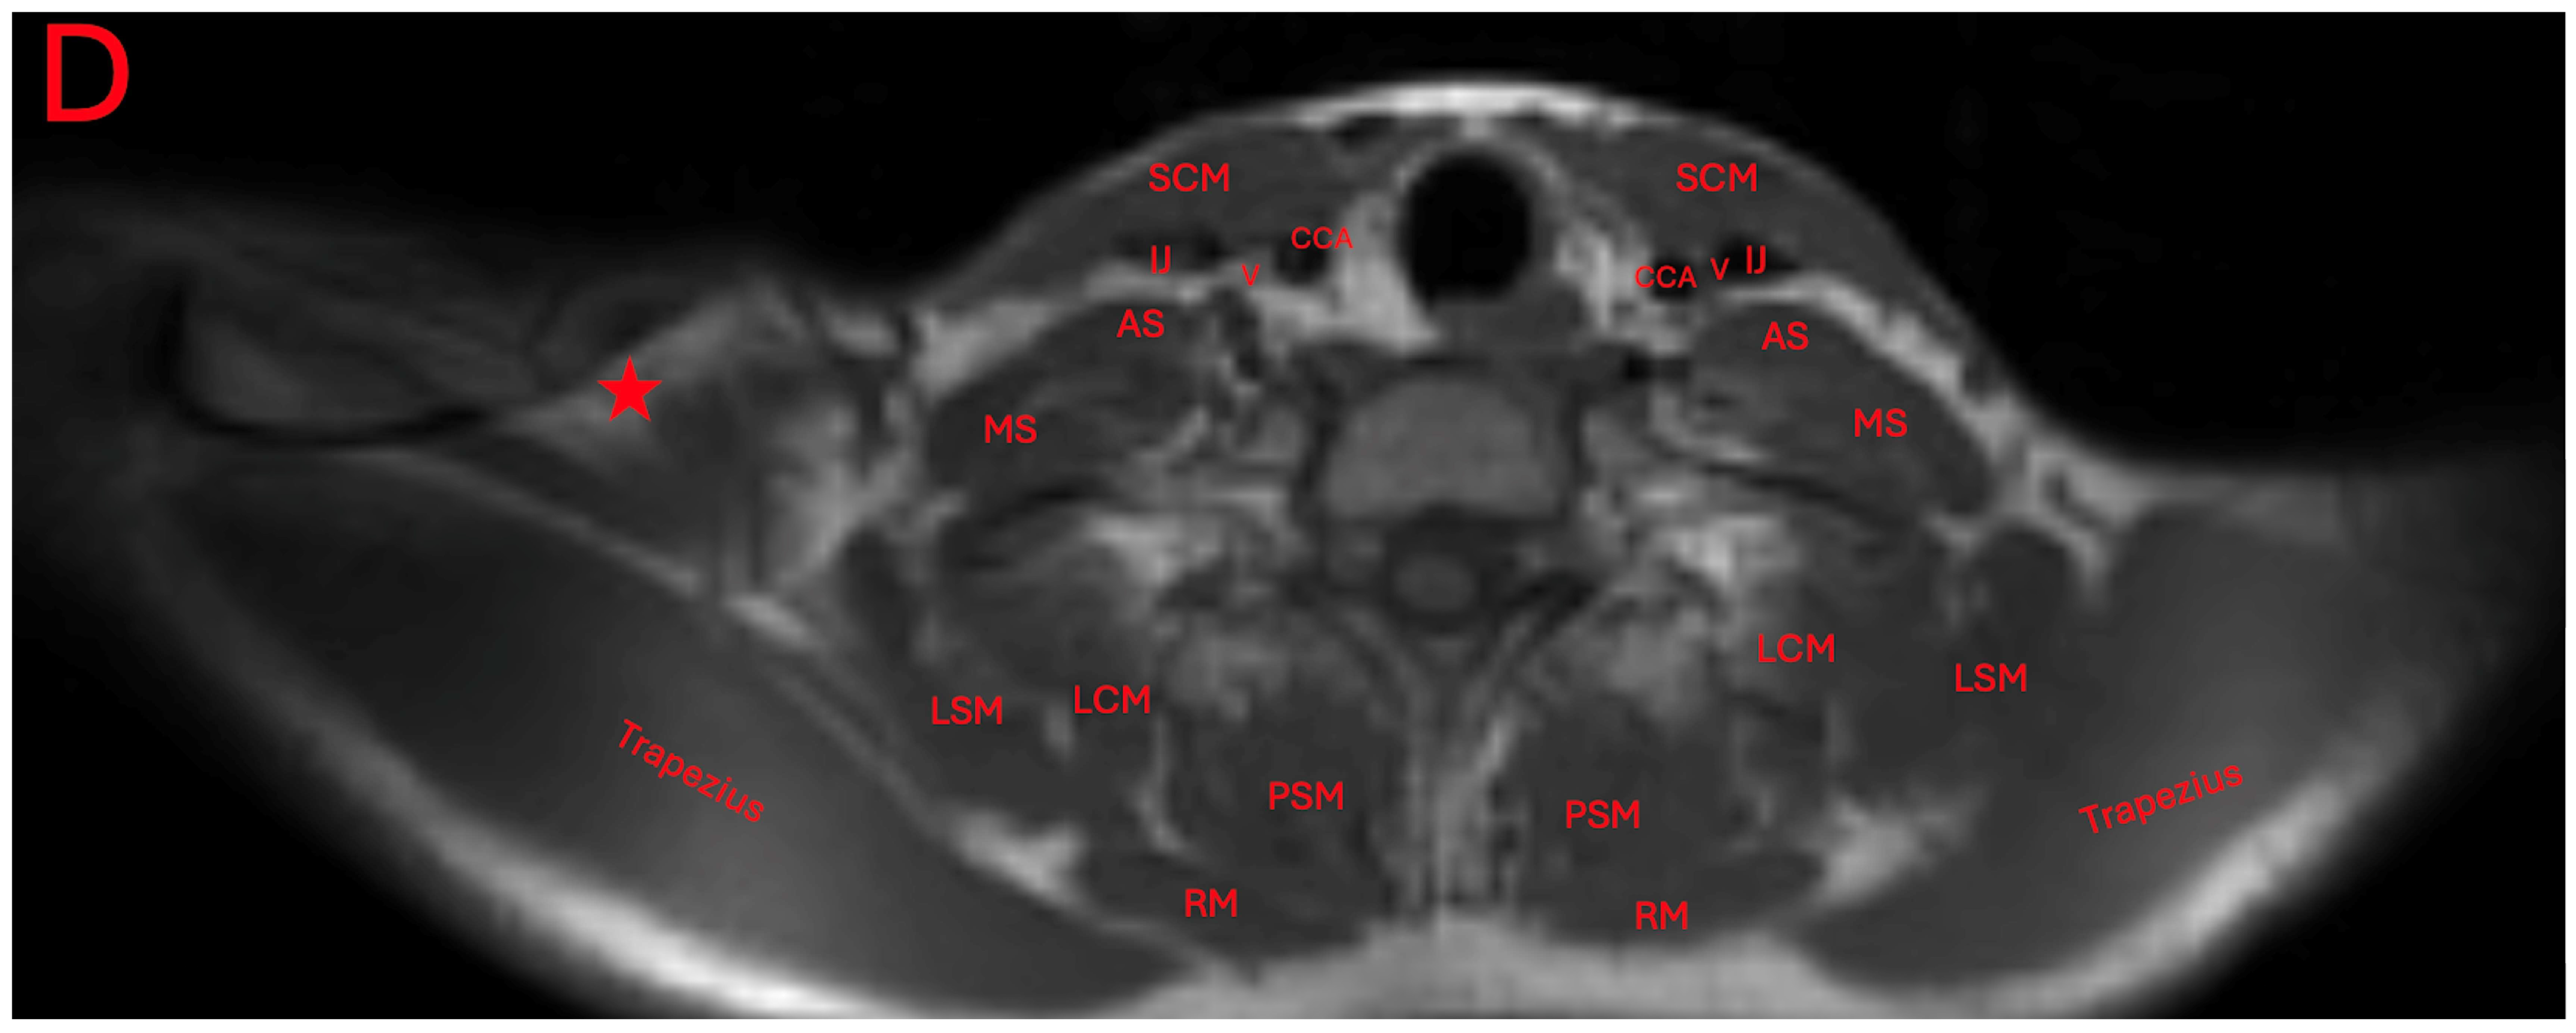

The patient was seen by an outside neurologist who performed an ultrasound of the right neck. This neurologist reported the presence of normal skeletal muscle inserting at the clavicle and blending with the trapezius. They additionally reported a cervical band subjacent to the brachial plexus, and a transverse artery traveling between the upper and middle trunks. An MRI was ordered to further characterize the accessory muscle. Its location was found to be superior to the neurovasculature bundle (Figure 2 and Figure 3).

The presence of this accessory muscle can also be observed adjacently to the trapezius and levator scapulae muscles, and attached to an irregular protuberance of the clavicle (Figure 4A–D).

Figure 4. Axial T1-weighted MRI imaging of the patient’s neck and shoulder (AD). Red stars indicate the position of the levator claviculae muscle. The other abbreviations are the common carotid artery (CCA), vagus nerve (V), internal jugular vein (IJ), sternocleidomastoid (SCM), anterior scalene muscle (AS), middle scalene muscle (MS), omohyoid (OMO), levator scapulae muscle (LSM), longissimus cervices muscle (LCM), paraspinal muscle (PSM), and rhomboid muscle (RM).